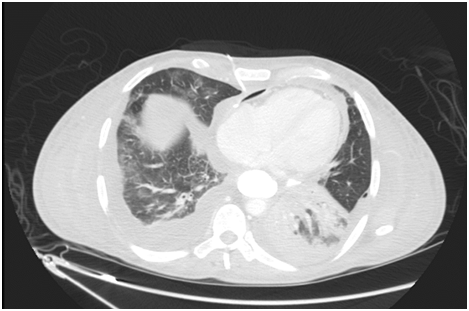

On initial examination, the patient was found to have borderline BP (SBP 101, DBP 60), diminished air entry at the bilateral right and left inferior lung fields. The cardiac examination was remarkable for normal S1, S2 and distended jugular venous distension of 10cm. Chest radiography (CXR) showed an intact esophageal stent along with radiolucent rim surrounding the cardiac silhouette (Figure 1). Echocardiogram (echo) revealed an air gap sign echoic dense space at the anterior and basal part of the heart consistent with the pneumopericardium with no signs of tamponade (Figure 2).  Computed tomography (CT) scan chest confirmed the presence of pneumopericardium in anterior pericardium along with left sided mediastinal pocket of air with foci of gas above the esophageal stent likely communicating with the pericardium (Figure 3). Given the clinical and radiological evidence of the symptomatic large pneumopericardium, we consented the patient on an emergency pericardiocentesis. Goals of care were discussed with the patient and his family and the patient opted interventional care measures. A following pericardiocentesis (with off label CT guidance) right sided parasternal approach (marked at the right 5th intercostal space with angulated entry projection of 70 degree medially with 27mm depth) was performed successfully with aspiration of 70ml of air followed with frothy blood-stained aspirate. The gentleman symptoms resolved immediately with picked up BP (SBP 123,DBP 67) and pigtail kept and secured in place for 5days without any complications.  Thereafter, a follow up echo and CT scan repeated and showed bright improvement in the clinical status (Figures 4 & 5) respectively.

Figure 3 CT axial cut shows anterior Pneumopericardium with proposed entry point at the right 5th Inter Costal Space with medial inclination of 70 degree and 27 mm to reach PE.